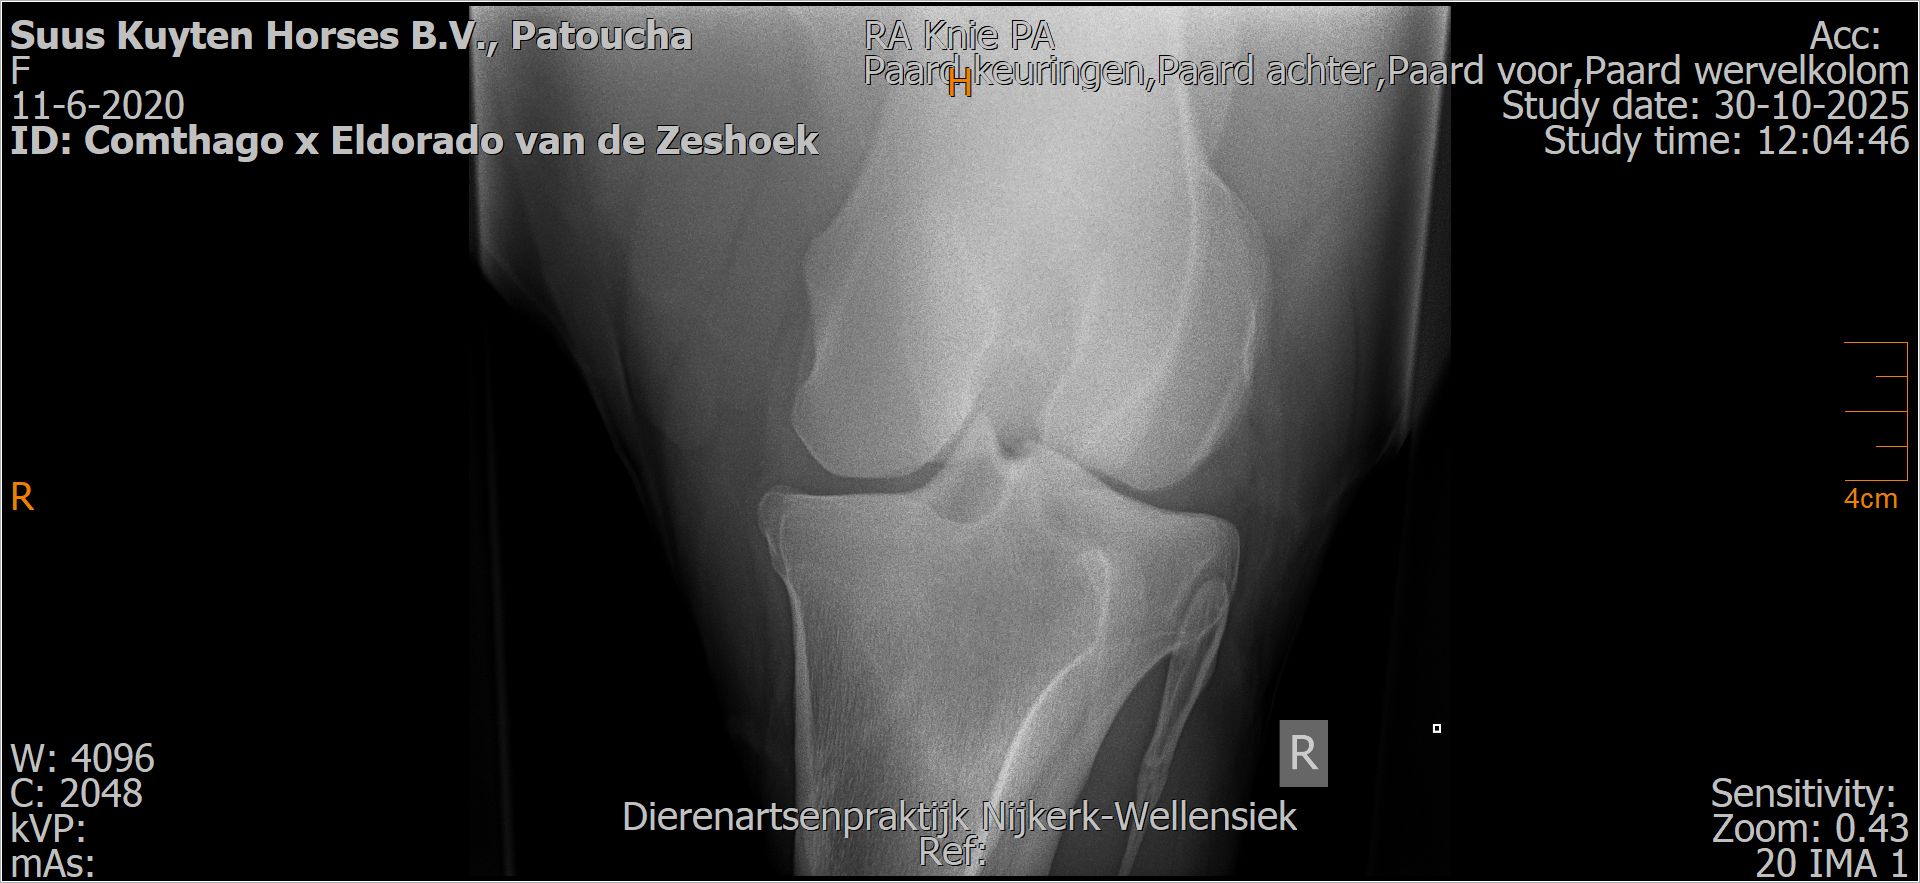

Patoucha

Leeftijd:

7

Röntgenfoto’s